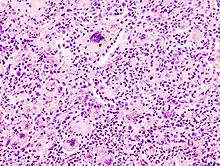

• TOUTON-Riesenzelle - Schaumzellen, bei denen um eine kleine schaumfreie Insel mehrere Kerne ringförmig angeordnet sind, Vorkommen z.B. bei juveniler Xanthogranulomatose, siehe Abb.

Fremdkörper-Riesenzellen bei Aspirationspneumonie, Autopsiepräparat, H&E.